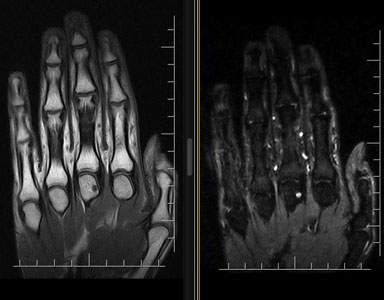

Grazie alle diverse pesature di immagine che possono essere ottenute tramite una scansione RM, si apprezzano, per esempio, a livello lombare ernie/protusioni discali, schiacciamenti vertebrali, crolli, o sofferenze dell’osso intraspongioso; a livello invece osteoarticolare si riesce ad evidenziare con grande precisione i legamenti e i tessuti muscolari che compongono l’articolazione oggetto di studio e quindi, le eventuali patologie correlate a queste, come ad esempio artrosi, lesioni legamentose e muscolari, osteocondropatie.

risonanza magnetica alla mano